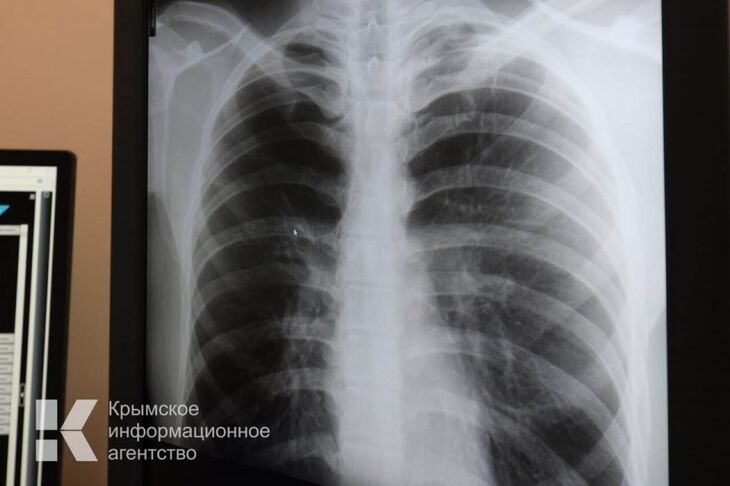

Крымчане стали реже болеть пневмонией

По состоянию на начало ноября в Крыму зарегистрировали почти 9 тысяч случаев заболевания внебольничной пневмонией. Об этом корреспонденту Крымского информационного агентства сообщил заместитель руководителя Роспотребнадзора РК Дмитрий Крутиков.

«Уровень заболеваемости в сравнении с прошлым годом снизился на 14,7%. Количество заболевших внебольничной пневмонией к 1 ноября составил 8 932 случая», - отметил Крутиков.